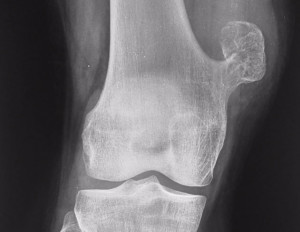

Остеохондрома

Это также доброкачественное опухолевидное образование. Оно представляет собой костный выступ. Он покрыт шапочкой из хрящевой ткани, а внутри заполнен костно-мозговым содержимым. Это образование самое распространенное. Часто выявляется у ребенка или подростка.

Такая опухоль может протекать бессимптомно, человек случайно обнаруживает шишку на правой или левой ключице. Он может не жаловаться, что она болит. Крупное образование может сдавливаться нервы, сухожилия, мышцы.

Если появилась такая шишка, следует обратиться к ортопедам. Есть один способ лечения – операция, необходимо удалить образование в границах здоровых тканей. Показание к операции – нарушение функции руки, деформация скелета, быстрый рост. Если нет таких показаний, осуществляется наблюдение, основанное на периодическом проведении рентгена. Суть операции в надрезе и краевой резекции, удаляется также основание ножки опухоли. Чаще всего прогноз благоприятный.

Экзостоз ключицы. Экзостозы ключицы в большинстве случаев характерны для детей и обнаруживаются до 20 лет. Их называют остеохондромами, которые относятся к числу доброкачественных опухолей скелета. Экзостоз представляет собой костно-хрящевой нарост на поверхности ключицы и образует с ней единое целое.